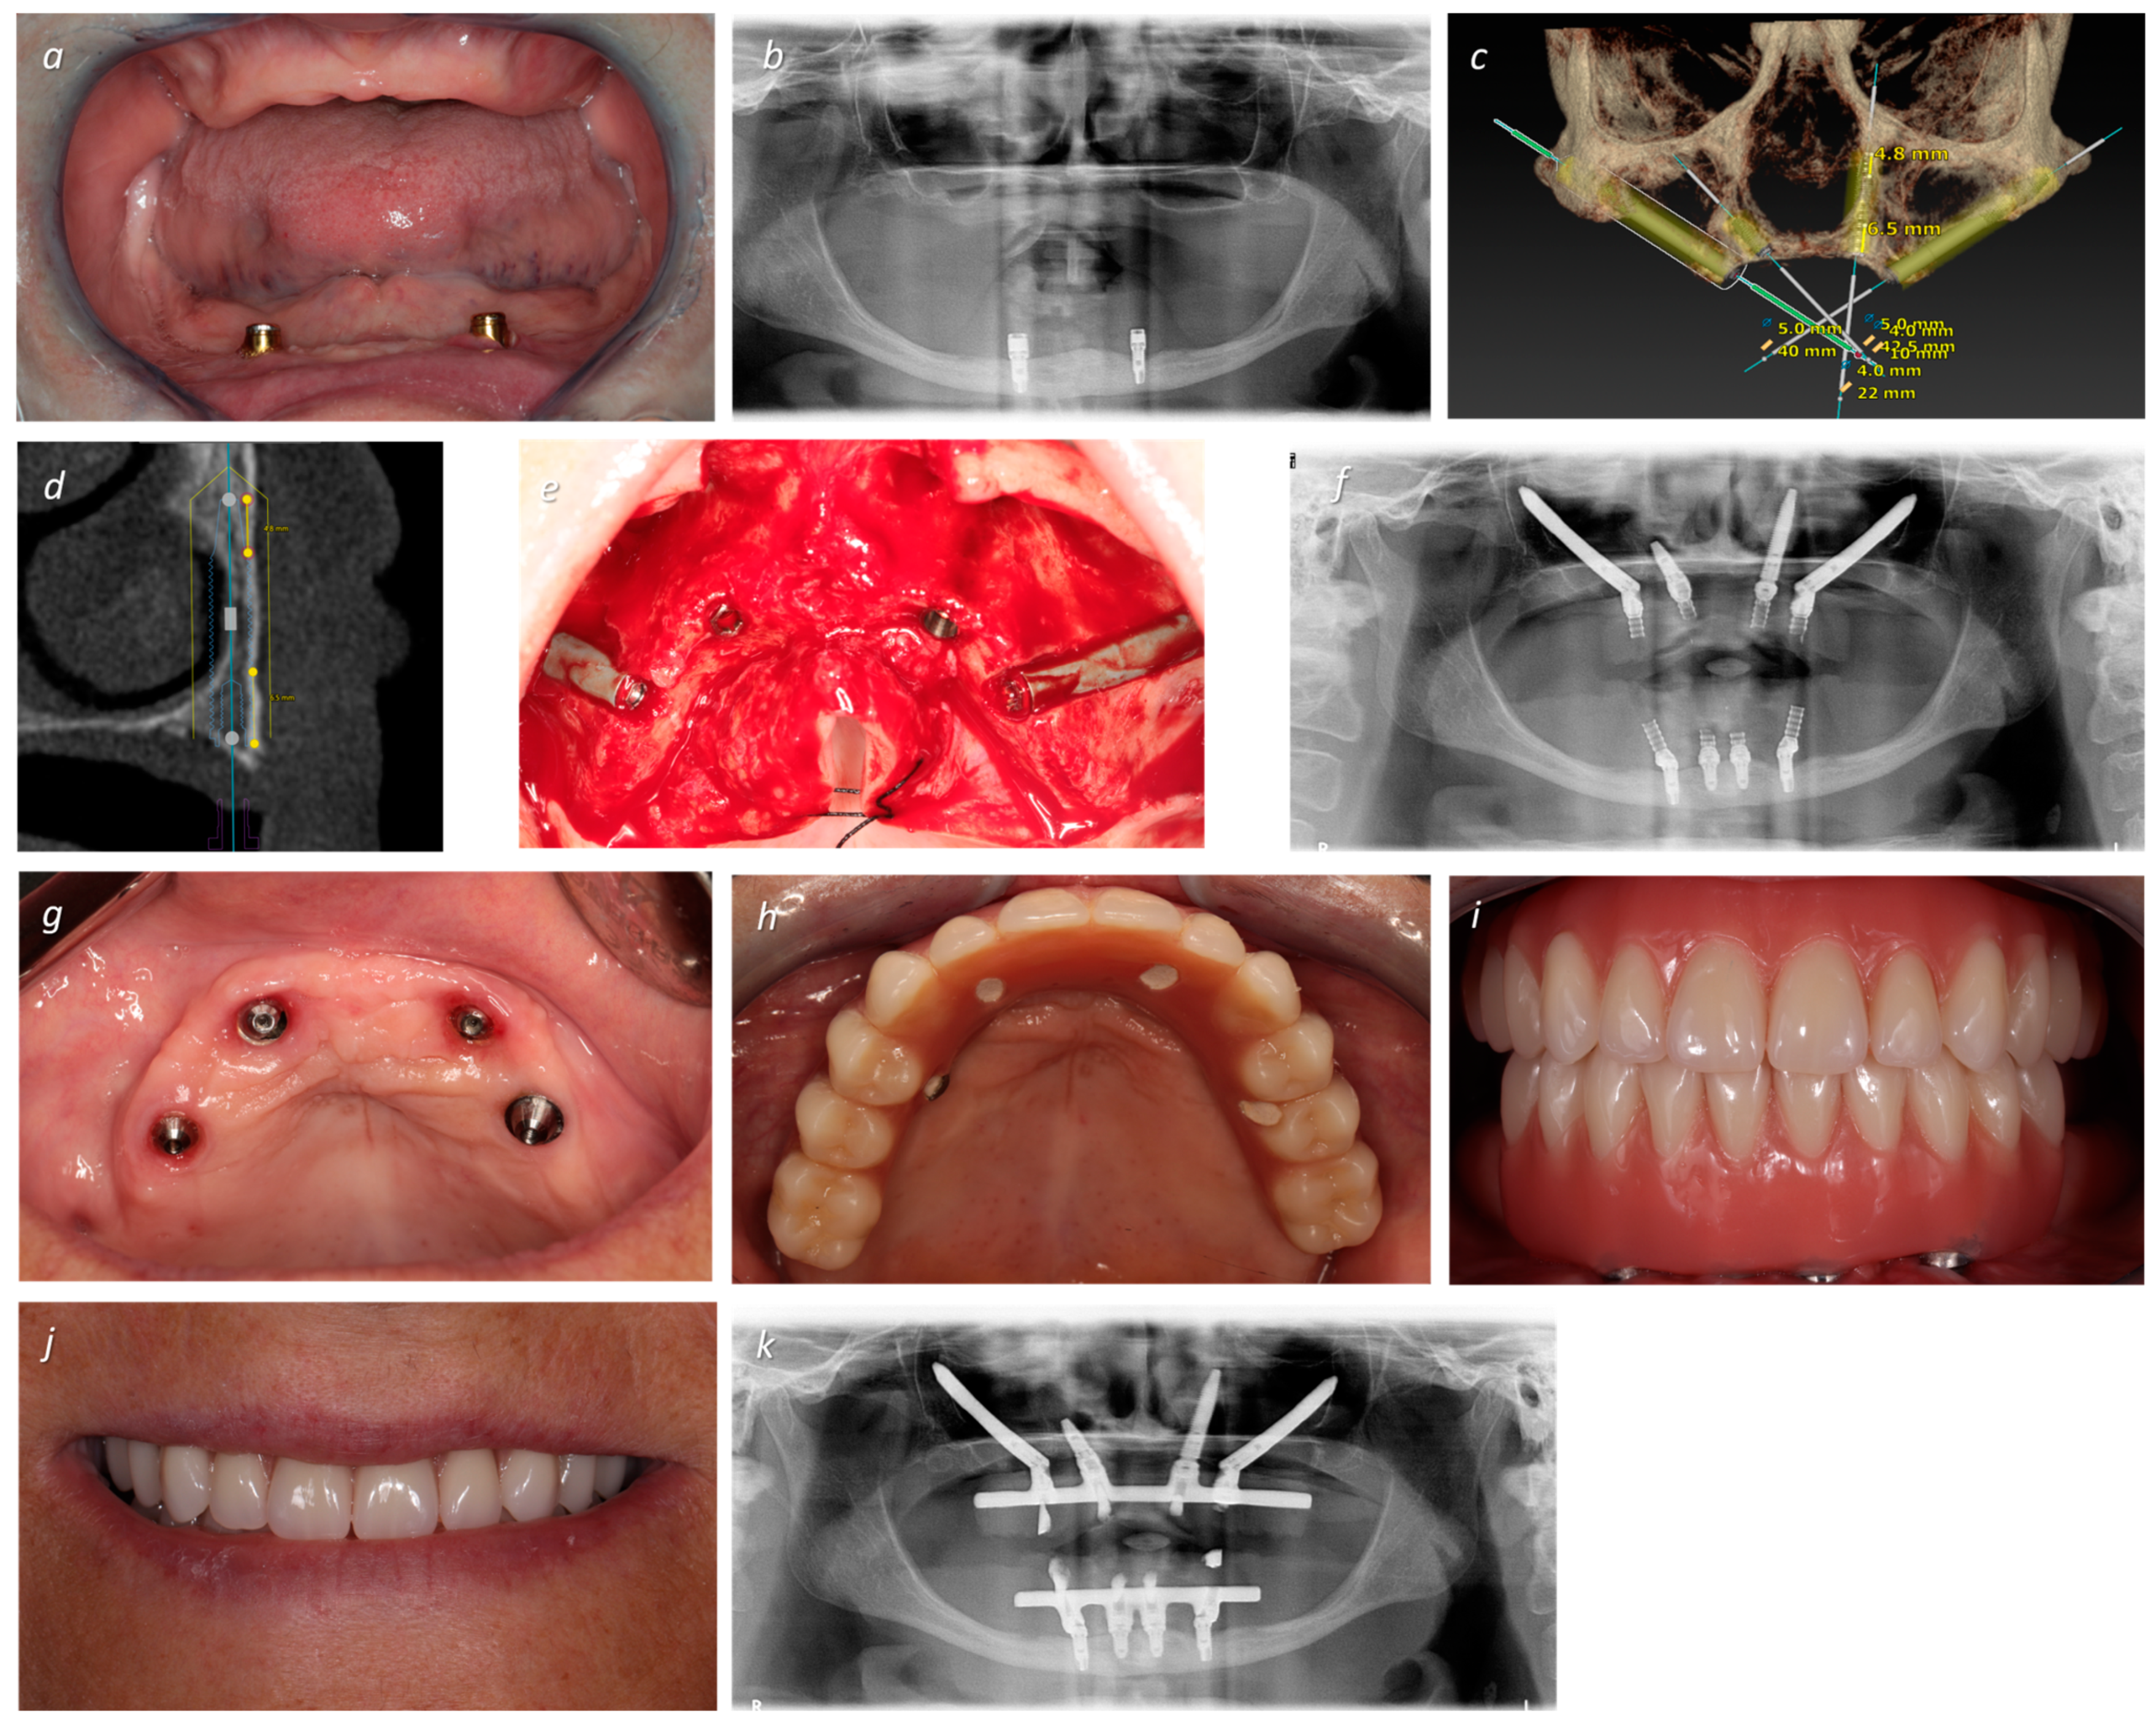

| 3 | EM 0° 5 × 40 | S 4 × 10 | T 3.75 × 22.5 | EM 0° 5 × 40 | 64 | F | 3 | I | NG | +50 |